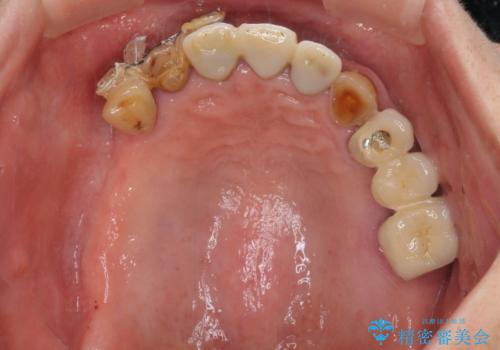

- 前歯の部分矯正や仮歯に置き換えるなど、治療途中のまま放置してしまったとのことで来院された患者様です。

骨格的に下顎骨が前方にあり、歯列の幅も下顎の方が大きいため、奥歯に負担のかかりやすい咬合でした。

大臼歯部は、上下左右ともに咬合により問題が生じており、骨格的な問題から積極的な治療をするべきか判断の難しい状況でした。

臼歯部は痛みが生じている歯に絞って処置を行い、それ以外については手を加えず、現状維持を心がけることとしました。

前歯部については抜歯が必要な歯を抜歯し、インプラントやブリッジなどにより補綴治療を行うこととしました。